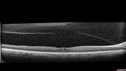

Perifoveal Microaneurysm - Not Diabetic (also reticular pseudodrusen)365 views87 year old female with fluctuating macular edema in the right eye from a perifoveal MA. (no treatment). VA 20/40 OU00000